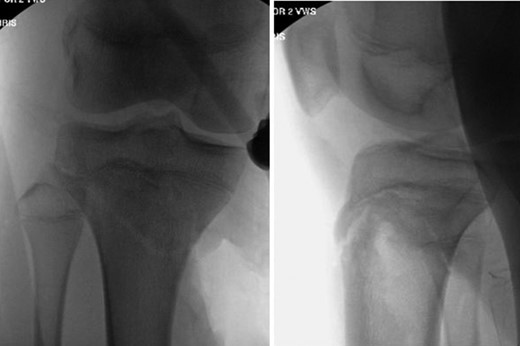

Patient is a 14-year-old male who slipped and fell while jumping off of a diving board and landed onto a flexed right knee. The patient was stable on presentation and neurovascularly intact with the knee locked in flexion. Skin was tenting anteriorly over the tibial tubercle and his compartments were swollen but compressible. A single plain film view (Fig. 1) was obtained prior to orthopaedic consultation. Closed reduction under sedation and splitting was attempted in the ED with partial but unsatisfactory improvement. Post-reduction radiographs (Fig. 2) demonstrated a tibial tubercle fracture with extension through the entire proximal tibial physis with metaphyseal involvement posteromedially. We classified this as a type IV tibial tubercle fracture, Salter–Harris II variant. In conjunction with patient and family we planned for urgent closed versus open reduction and application of knee-spanning external fixator. Immediately prior to surgery in the pre-operative holding area, the patient noted increasing right leg pain. In the operating room (OR), a marked increase in swelling with tense skin was observed. Due to rapidly progressive swelling and nature of the fracture, the decision was made to proceed with a 4-compartment fasciotomy of the right leg. The medial-sided fasciotomy (Fig. 3) revealed significant bulging of the superficial and deep compartments; however, the anterior and lateral compartments were less swollen. The fracture was unable to be closed reduced intraoperatively, therefore proximal extension of the medial fasciotomy wound was performed to open and reduce the fracture under direct visualization. Anatomic reduction was achieved and a knee-spanning external fixator was applied (Fig. 4). Approximately 72 hours later the patient was brought back to the OR for irrigation and debridement, lateral wound closure, and medial wound vacuum placement. Another 72 hours later, he returned to the OR for removal of the external fixator, ORIF, and split-thickness skin grafting of the medial fasciotomy site. An anterolateral approach was used with a 3.5 mm proximal tibial locking plate (Fig. 5). At most recent follow-up (Fig. 6), six months post-op, the patient is pain free, ambulating without assistive device, and has returned to all desired activities.

AP and lateral intraoperative fluoroscopic images following ORIF with proximal tibial locking plate.